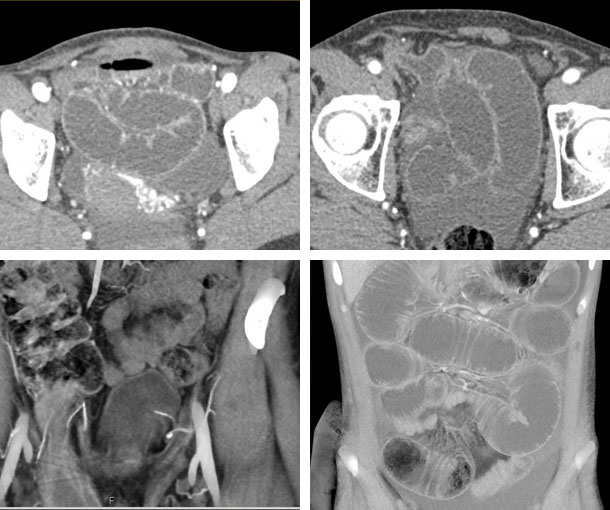

Inguinal Hernia CT Findings

Direct:- Protrusion of tissue through the transversalis fascia (Hesselbach triangle)

- Hernia sac is pushed medial and inferior to the inferior epigastric vessels

- Compressed and stretched inguinal canal

- Inguinal canal fat is pushed into “moon crescent” sign

- More common

- Protrusion of tissue through internal inguinal ring into inguinal canal

- Lateral to the Hesselbach triangle

- Lateral and superior to the inferior epigastric vessels

- In males, they can extend into the spermatic cord and scrotum; females, into the labia majora